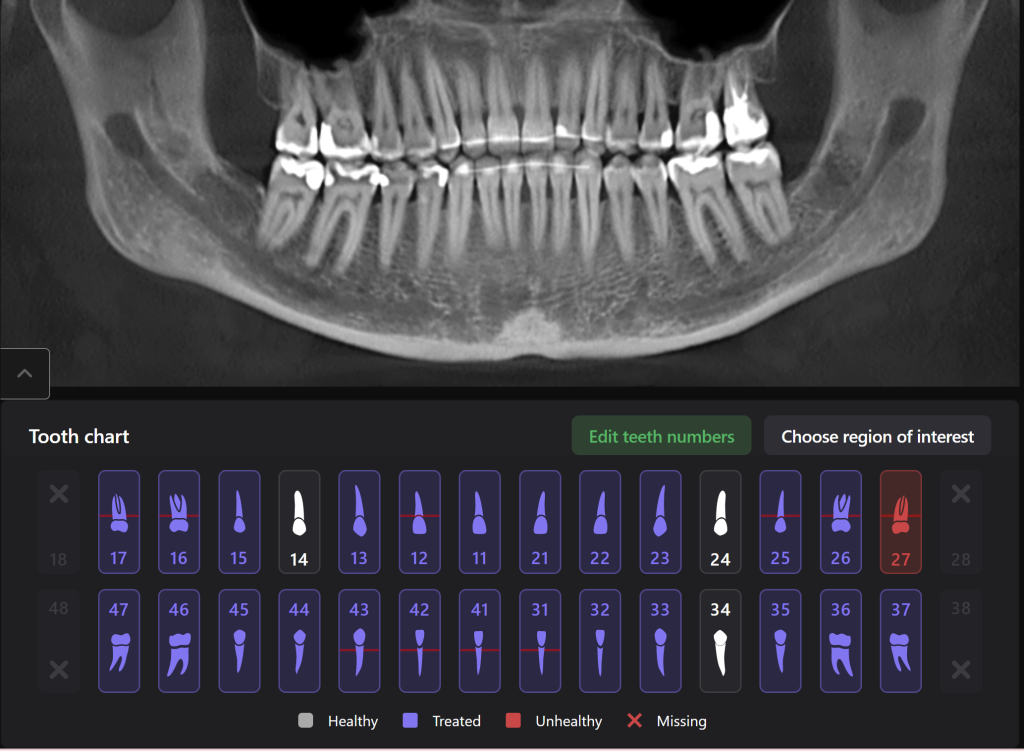

Diagnocat is an artificial intelligence system, one of its advantages being assistance in planning therapeutic dental treatment and identifying signs of caries

Diagnocat determined not only the presence, but also the localization of the focus of radiolucency of enamel and dentin, which was correctly indicated as “signs of caries” in the report

Please note that despite the fact that the radiolucent area is poorly visible when viewing CBCT, Diagnocat reflected in the report the presence of signs of caries and accurately indicated the localization

The presence of a structured report allows the clinician to set up the patient for timely treatment and build a consistent plan for therapeutic dental treatment